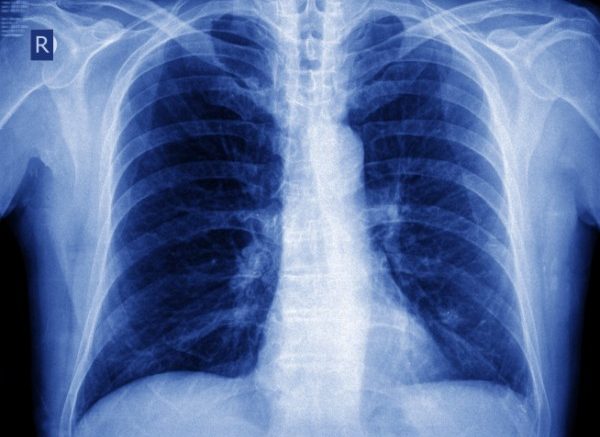

Pescara: simposio sul nodulo polmonare. Esperti a confronto per parlare del tema “Il nodulo polmonare solitario: un tema antico che torna di attualità”. Gli specialisti spiegano che i noduli polmonari sono molto diffusi nei fumatori incalliti e di solito si presentano sotto forma di cicatrice, granuloma, oppure un’infezione, meno spesso un tumore. Se vi siete sottoposti ad un esame al torace ed avete scoperto di avere un nodulo al polmone è meglio rivolgersi allo specialista. Comunque i dati dicono che in Italia su 5 mila soggetti esaminati, con più di 50 anni e forti fumatori, vengono trovati noduli nella metà dei casi, ma alla fine solo 50 risultano tumorali. Nella maggior parte dei casi sono benigni, dovuti, per esempio, a esiti cicatriziali di precedenti infiammazioni, come broncopolmoniti, a granulomi, oppure sono segno di infezioni come la tubercolosi. Altre volte, sono, invece, di natura maligna e quindi sono una spia di un tumore al polmone o di metastasi polmonari di tumori di altra provenienza. La Tac , più che la radiografia , consente di rilevare noduli di dimensioni inferiori al centimetro nonché diversi parametri, tra cui densità, forma, presenza di calcificazioni e anche ricostruire l’aspetto volumetrico del nodulo, permettendo di valutarne con precisione la crescita nel tempo. L’analisi di tutti questi parametri orienta la diagnosi, evitando, in molti casi, inutili esami e tanta ansia. La prevenzione è anche in questi casi fondamentale e la prima regola è quella di non fumare e se si è stati fumatori a lungo si può considerare l’opportunità di controlli periodici con la Tac dopo i 50 anni. Questo esame permette una diagnosi precoce di tumore al polmone nel 75% dei casi e cià aumenta le possibilità di guarigione.